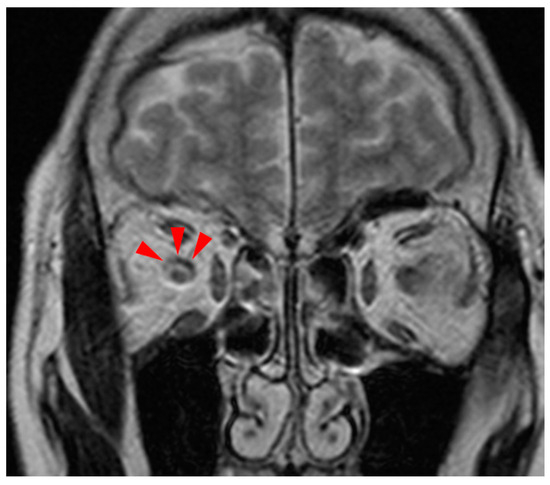

A Case of Mycoplasma Infection with an Atypical Presentation of Abducens Nerve Palsy, Erythema Multiforme and Polyarthritis without Respiratory Manifestations

by Kiyomi Yoshimoto, Masaki Matsubara, Tadanao Kobayashi and Kenji Nishio

Medicina 2024, 60(1), 36; https://doi.org/10.3390/medicina60010036 - 25 Dec 2023

Cited by 1 | Viewed by 5289

Mycoplasma pneumoniae is a self-propagating microorganism that commonly causes respiratory tract infections. It can also cause a variety of extrapulmonary symptoms with or independently of respiratory symptoms, such as skin lesions, arthralgia, myalgia, hemolysis, cardiac lesions, gastrointestinal symptoms, and central nervous system lesions, [...] Read more.

Mycoplasma pneumoniae is a self-propagating microorganism that commonly causes respiratory tract infections. It can also cause a variety of extrapulmonary symptoms with or independently of respiratory symptoms, such as skin lesions, arthralgia, myalgia, hemolysis, cardiac lesions, gastrointestinal symptoms, and central nervous system lesions, which are rare manifestations reported in approximately 0.1% of cases. In this study, we present a unique case of Mycoplasma-related abducens nerve palsy, polyarthritis, and erythema multiforme without respiratory disease. The patient was a 69-year-old woman who presented to our hospital with a skin rash, fever, arthralgia, and diplopia without respiratory symptoms. Brain magnetic resonance imaging showed optic neuritis on the right side, suggesting the diplopia was caused by right abducens nerve palsy. However, the etiologies of abducens nerve palsy were not revealed by the physical examination, blood biochemistry tests, or bacteriological examinations, including the cerebrospinal fluid examination obtained at admission. Mycoplasma infection was suspected from erythema multiforme revealed by a skin biopsy and polyarthralgia, and it was finally diagnosed according to elevated Mycoplasma particle agglutination (PA) antibodies in paired serum. Though minocycline did not improve her diplopia, the daily administration of 30 mg of prednisolone gradually improved her symptoms, and the Mycoplasma PA antibody titer, which was regularly measured in the clinical course, also decreased, suggesting a relationship between Mycoplasma infection and abducens nerve palsy. This is the first case of isolated abducens nerve palsy, which was reported as the only central neurological symptom in an adult patient with Mycoplasma infection. The mechanism or pathogenesis of CNS manifestations caused by Mycoplasma pneumoniae remains to be elucidated, and further investigation is needed. Hence, Mycoplasma infection is a common disease. Clinicians should be aware of the diverse manifestations, including abducens nerve palsy, of Mycoplasma infection and should consider Mycoplasma infection even in the absence of typical respiratory symptoms. Full article